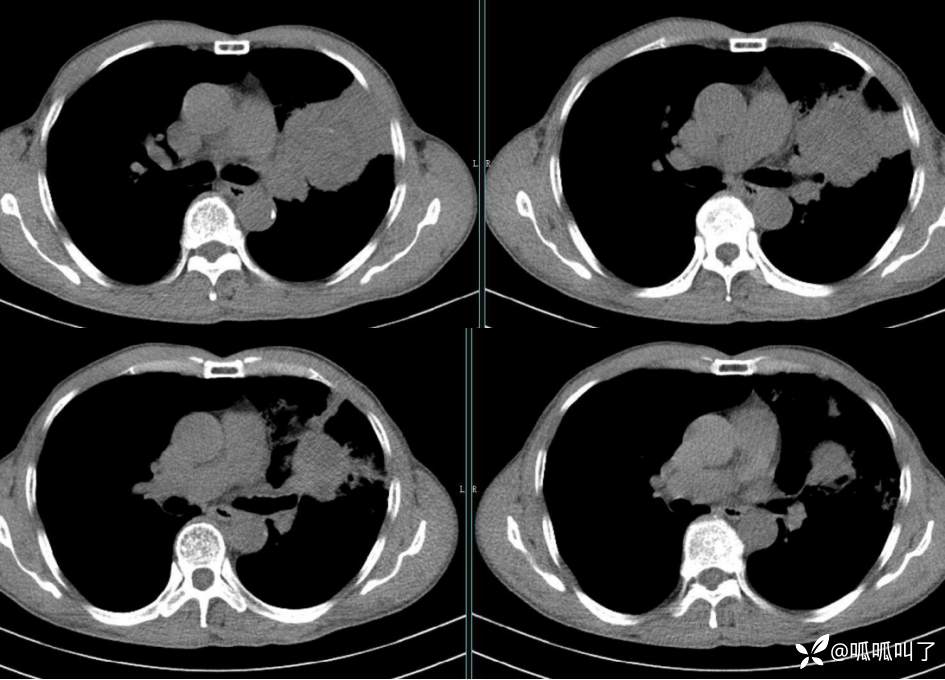

胸部CT平扫和增强: